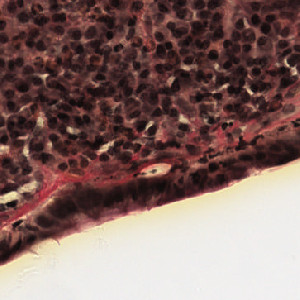

Van Gieson, Collagenous Colitis

Microscopic colitis is a type of inflammation of the colon that causes chronic non-bloody watery diarrhea. The disorder cannot be detected using normal colonoscopy, but is possible to detect by examining a biopsy of the colon tissue. Microscopic colitis can be distinguished into two subtypes, lymphocytic and collagenous. This APP addresses collagenous colitis, which is characterized by a thick layer of collagen in the colon tissue.

Thus, by quantifying the percentage of collagen in the colon tissue, a diagnosis can be determined.

Raw image of colon tissue.

Raw image showing the collagen border.